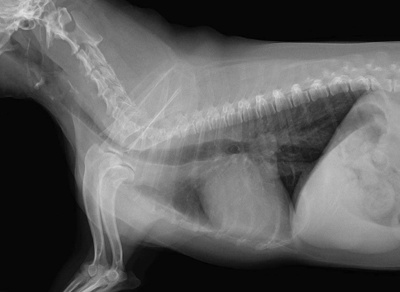

気管虚脱とは小型犬に多い病気で、気管が扁平化する病気で、気管が潰れることで咳やガチョウのようなガーガーいう呼吸を起こしたり、重症化すると呼吸困難で死亡してしまう怖い病気です。

進行性の病気なので、内科療法をおこなっていても症状は徐々に進んで行きます。